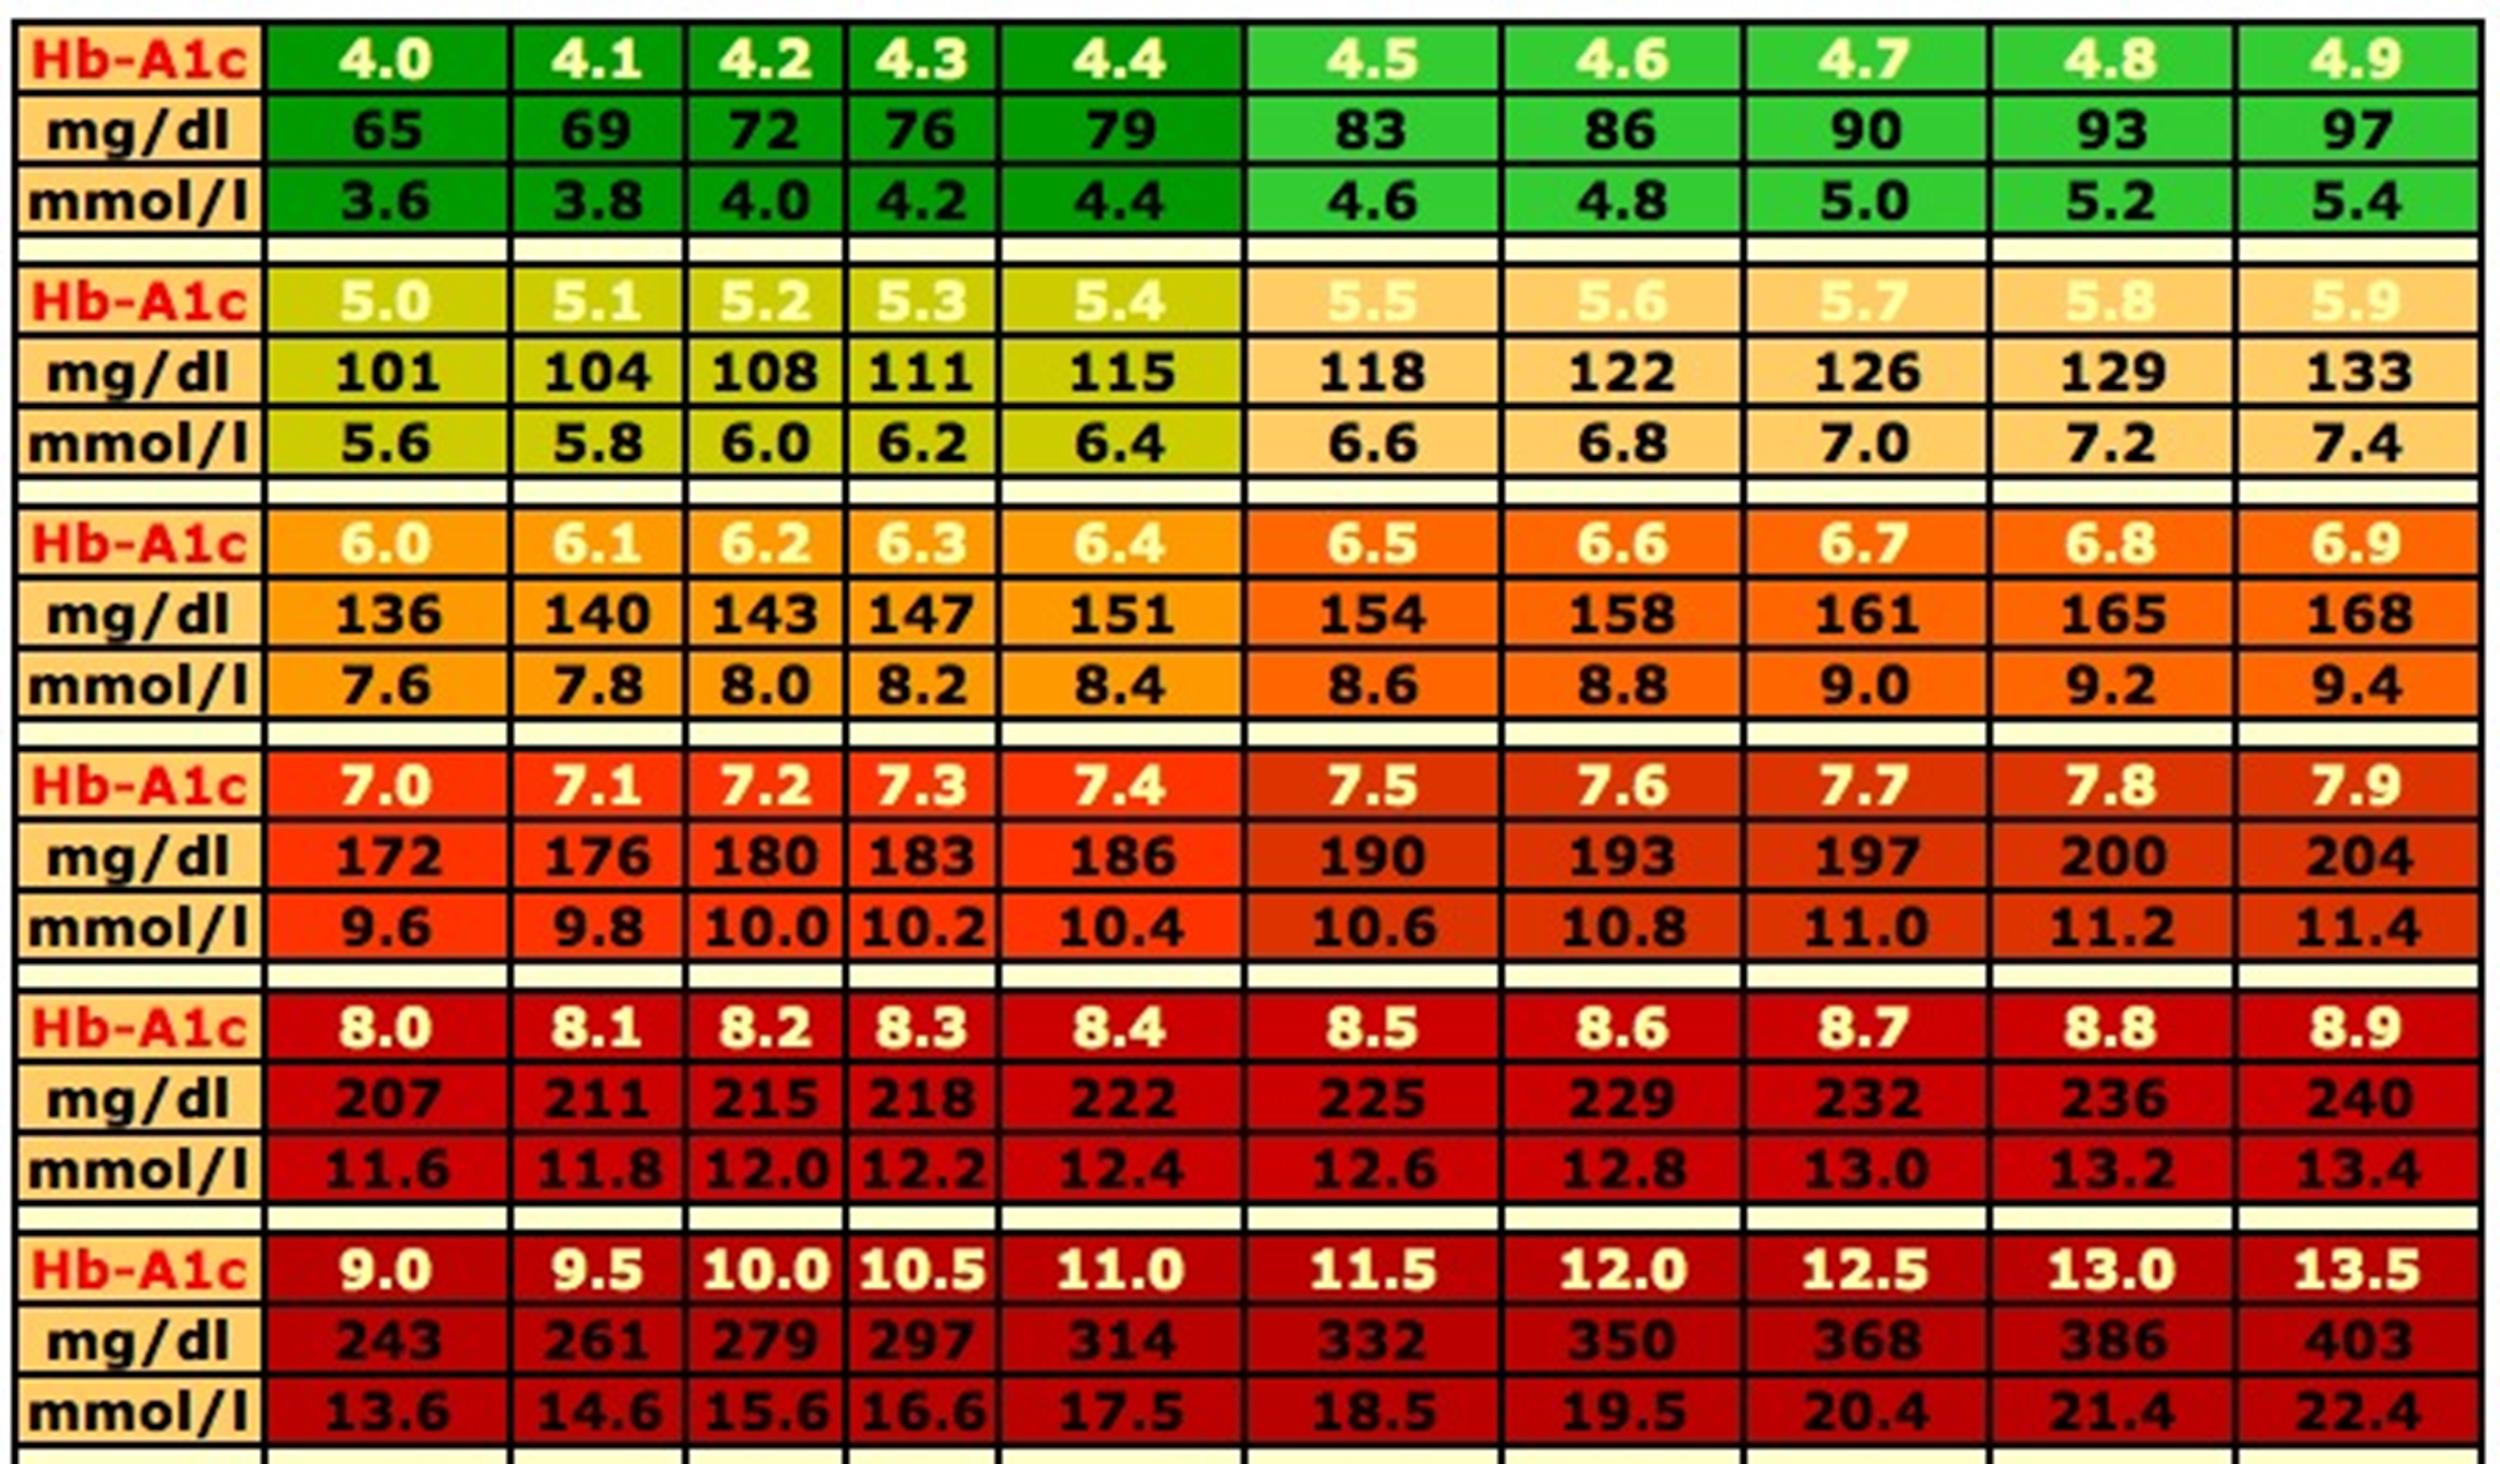

Blood Sugar Chart Understanding A1C Ranges Viasox

http://viasox.com/cdn/shop/articles/Diabetes-chart_85040d2f-409f-43a1-adfe-36557c4f8f4c.jpg?v=1698437113

25 Printable Blood Sugar Charts Normal High Low TemplateLab

25 Printable Blood Sugar Charts Normal High Low TemplateLab